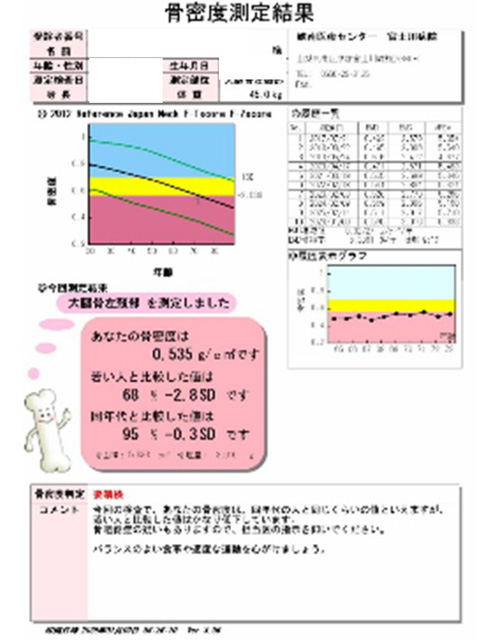

骨密度測定

骨を構成するカルシウムなどのミネラル成分の量をX線を用いて測定する検査です。主に骨粗しょう症の診断や投薬治療による骨量の変化に用います。当院では2つの異なるX線エネルギーを使用する測定法のDEXA法を用いて腰椎、大腿骨の骨密度を測定します。検査時間は10分から15分くらいになります。